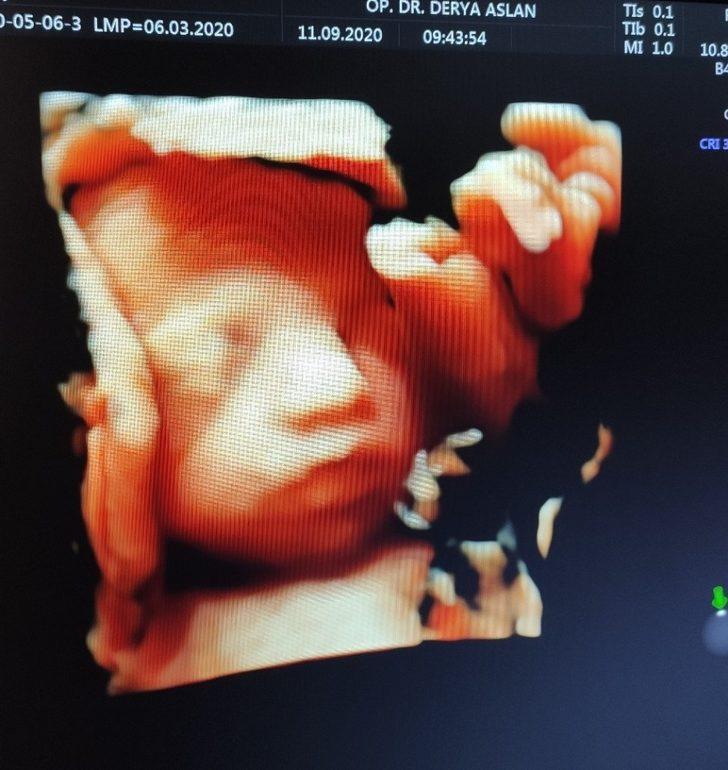

Tüm dünyayı etkisi altına alan Kovid-19 pandemisi insan sağlığını tehdit etmeye devam ederken, kısıtlama kararları ile evlerde geçirilen süreyi uzatıyor. Kadın Hastalıkları ve Doğum Uzmanı Op.Dr Derya Aslan, korona virüsü nedeni ile anne adaylarının da olumsuz yönde etkilendiğini ve kendi sağlığına dikkat etmeleri tavsiyesinde bulundu.

Korona virüsün anne adayları üzerindeki etkisi ve neler yapmaları gerektiğini anlatan Kadın Hastalıkları ve Doğum Uzmanı Op.Dr Derya Aslan Tüm dünyada olduğu gibi anne adayları da pandemiden etkilendi, gebelerin özel bir durumu olduğu için kendilerine daha çok özen göstermeleri gerekmektedir. Evde doğal gıdalardan oluşan bir beslenme şeklini saat aralıklı olarak düzenlenmesi gerekmektedir’’ diyerek evde her gebenin kendi sağlığına uygun gıdalardan beslenmesini tavsiye etti.